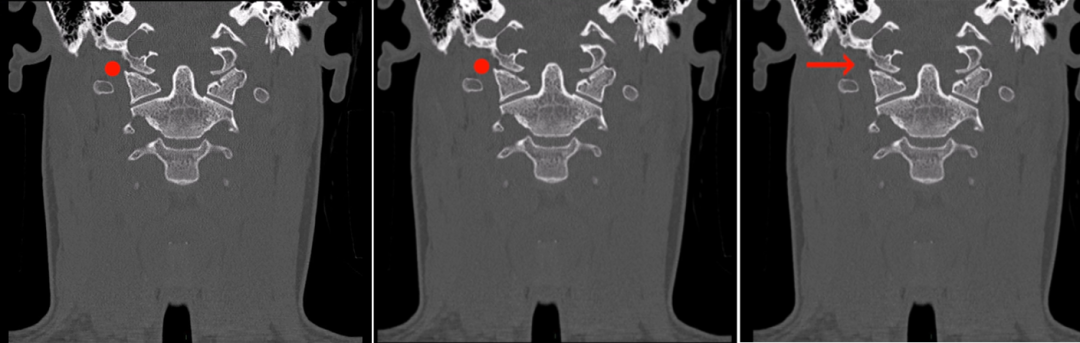

CT显示下斜坡和右侧枕骨髁部分损害